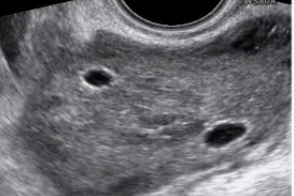

Guida al Counselling di Marzo 2026: torsione ovarica

vi presentiamo la guida al counseling di Marzo 2026 sulla torsione ovarica